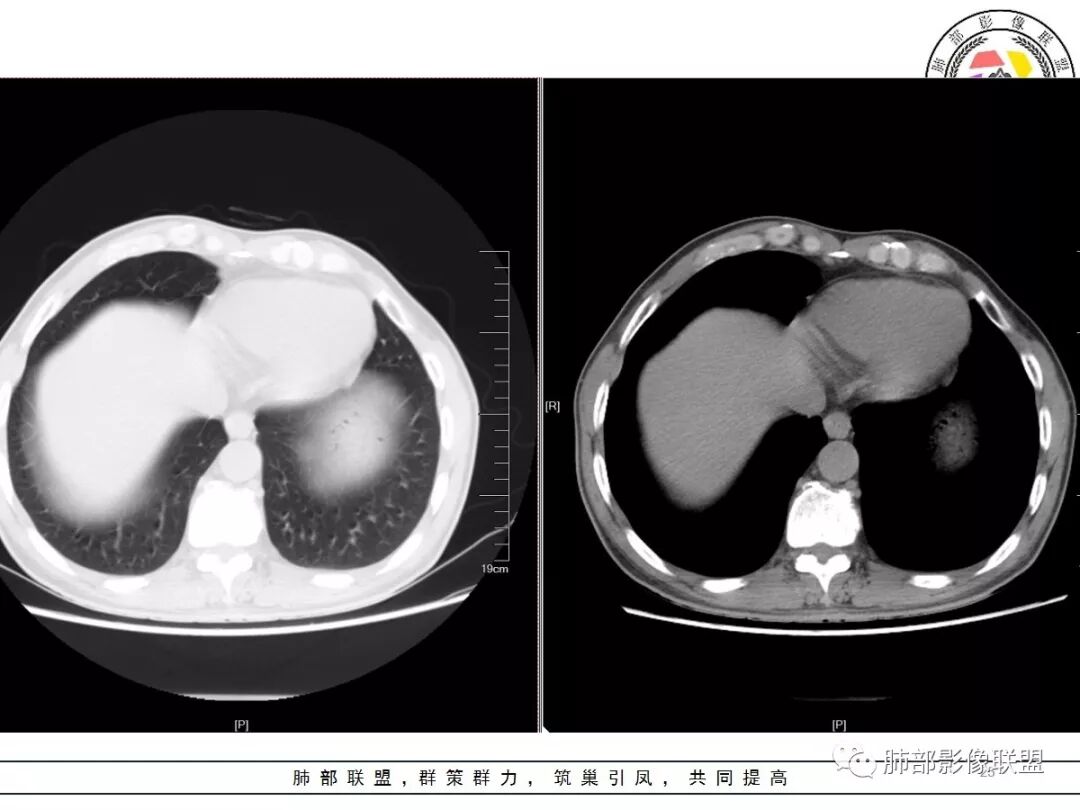

1.应该是双肺上叶多发结节,散在大小不等,密度不均,左上纵隔旁病灶环形强化,似乎都符合结核灶。

2.焦点在乎右肺上叶那个有点另类、有点儿一本正经的结节,密度均匀,未见支气管进入,部分圆隆浅分叶,长毛刺或棘状突起,胸膜有点牵拉,像个特立独行的新生物吗?

3.最不支持腺癌的一条是强化程度太轻。此外分叶不典型,还有那条牵张于肺表面的长长的细线影,不大像是在牵拽。

4.小结节新生物不大容易观察到液化坏死,如观察到液化坏死更容易想到的也是结核。

因此,完全排除肺鳞癌还有相当难度的。